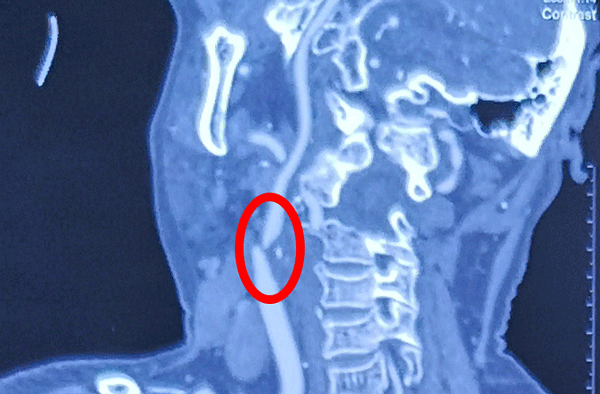

颈动脉有斑块、重度狭窄、CAS风险高,怎么办?

10月9日,张勤奕教授与渭南市第二医院联合救治一右侧颈动脉重度狭窄患者,顺利完成该院第三例CEA手术。